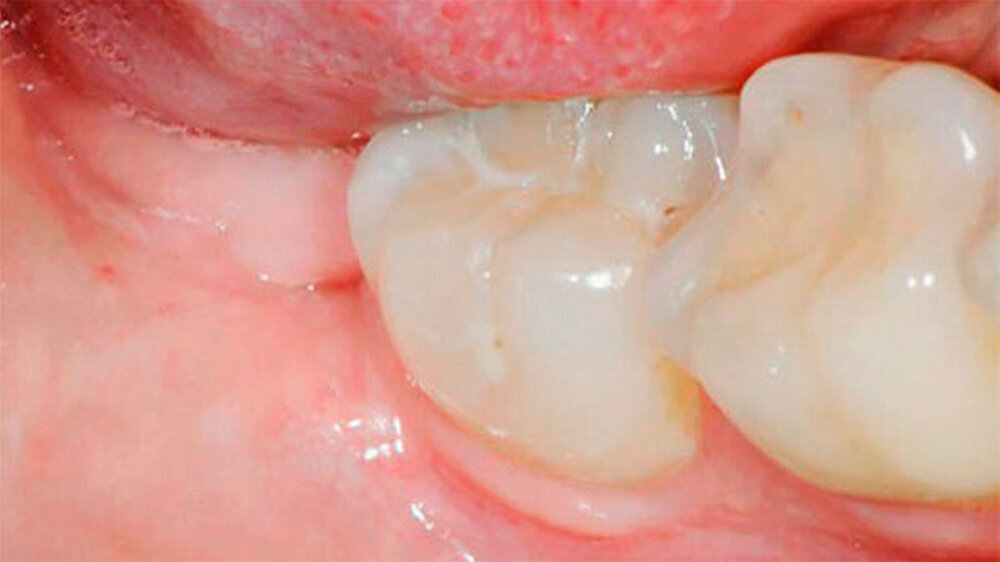

Nach einem Jahr wurde eine radiologische sowie eine klinische Nachkontrolle durchgeführt. Die Patientin war beschwerdefrei. Radiologisch war eine deutliche Migration des Wurzelblocks in kranialer Richtung sichtbar, die Wurzelspitze war radiologisch nicht über den Mandibularkanal projiziert. Die Schleimhaut war nicht durchbrochen (Abb. 1l und 1m). In diesem Fall sollte eine vollständige Entfernung des Wurzelrests angestrebt werden.